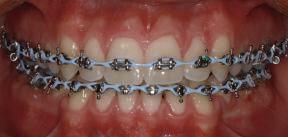

Dental Tribune Bulgarian Edition / октомври 2022 г.22 клиничен случай | ортодонтия 14-и месец В горната и долната челюст са поставени последни стоманени дъга с омега луп и тай бек – 17 x 25 SS с четвъртито сечение. Назначени е ластик за средната линия в комбинация с клас 3 ластик (1/4”, 6 1/2 oz). Контролни рентгенографии 13-и месец Екстракционните пространства са затворени. Направена е контролна панорамна снимка за оценка позицията на корените. Взето е решение за презалепване на брекетите на 12, 22 и пръстените на 36 и 46. 21-ви месец Средната линия в горната и долната челюст съвпадат. Ластиците са спрени. Свалени са пръстените и брекетите в горната и долната челюст, зигзаг ластици не са използвани поради благоприятните оклузални взаимоотношения. Фиг. 11j Ортопантомография в края на лечението. Фиг. 11k Телерентгенография след края на лечението. Фиг. 11l Анализ на телерентгенографията след лечението. Фиг. 11m Последователност на дъгите в горната и долната челюст Фиг. 11n Суперимпозиция на PreOp и PostOp ортопантомографии. 10-и месец Затварянето на пространствата е предвидимо и контролирано, без да се отварят пространства в зъбната дъга. Фиг. 8a Фиг. 8b Фиг. 8c Фиг. 8d Фиг. 8e Фиг. 10a Фиг. 10b Фиг. 10c Фиг. 10d Фиг. 10e Фиг. 9a Фиг. 9b Фиг. 9c Фиг. 9d Фиг. 9e Фиг. 9f Фиг. 11a Фиг. 11f Фиг. 11j Фиг. 11l Фиг. 11m Фиг. 11n Фиг. 11k Фиг. 11g Фиг. 11h Фиг. 11i Фиг. 11b Фиг. 11c Фиг. 11d Фиг. 11e

Dental Tribune Bulgarian Edition / октомври 2022 г. 23клиничен случай | ортодонтия реклама Лечението е продължило 21 месеца. Проведено е домашно избелване с индивидуални шини. За автора: Д-р Радой Димитров завършва с отличие Факултета по дентална медицина към МУ–София през 2015 г. В продължение на 5 години работи в няколко водещи практики в София, като през 2019 г. заедно със своята съпру га д-р Траяна Димитрова основават собствена практика в гр. Гоце Делчев –Dimitrovi Dental Care. Посещава редица курсове за повишаване на квалификаци ята, но най-сериозен тласък в развитието на ортодонтската си практика получава след завършването на комплексната ортодонтска програма, воде на от д-р Иван Горялов, базирана на дисциплината „Алекзандър“ – система с повече от 50 години опит в целия свят. Д-р Димитров е член на Българския изследователски клуб „Алекзандър“. Взе ма участие като гост-лектор в симпозиума с международно участие The Power of the Alexander Discipline, който се проведе на 14–15.05.2022 г. С д-р Ди митров можете да свържете на тел. +359885 252 025. Заключение Представеният случай е ярък пример за възможностите и красо тата на дисциплината „Алекзандър“ – приложен е утвърден под ход с ясни правила и са постигнати очакваните цели. Резулта тът ще бъде дългосрочно стабилен, тъй като са спазени всички правила, които се отнасят към максимално комфортната пози ция на зъбите в края на лечението. Постигнати са красива усмив ка и стабилна оклузия. ПОСТИГНАТИ РЕЗУЛТАТИ ОТ ЛЕЧЕНИЕТО 1. Коригирана ръбцова захапка 2. Коригирана клас 3 захапка в областта на ку чешките зъби 3. Коригирана кръстосана захапка в дисталните участъци 4. Коригиран овърджет и овърбайт 5. Разширена е горната зъбна дъга 6. Подредени зъби в горната и долната челюст 7. Постигната е стабилна захапка с множество контакти в ЦО 8. Драматично е подобрена дъвкателната функ ция 9. Подобрена е линията на усмивката ДРУГИ ПРОВЕДЕНИ ДЕНТАЛНИ ПРОЦЕДУРИ 1. Домашно избелване на зъбите 2. Екстракция на мъдреците Фиг. 12a Фиг. 12b Фиг. 12c Фиг. 12eФиг. 12d Фиг. 12f Фиг. 12g Информация за дати, цени и отстъпки www.bracescourses.com 0889 22 55 01 Практически курсове лектор д-р Иван Горялов Дисциплината „Алекзандър“ ПЪТЯТ КЪМ СУПЕРУСМИВКИТЕ 100% връщане на цялата сума, ако не сте удовлетворени след преминаване на Ниво 1 Директно и индиректно залепяне на брекети Анализ, диагноза и план на лечение Лечение на клас 2 дълбока захапка Екстракционно лечение Лечение на клас 3 отворена захапка НИВО 5НИВО 1 НИВО 2 НИВО 3 НИВО 4